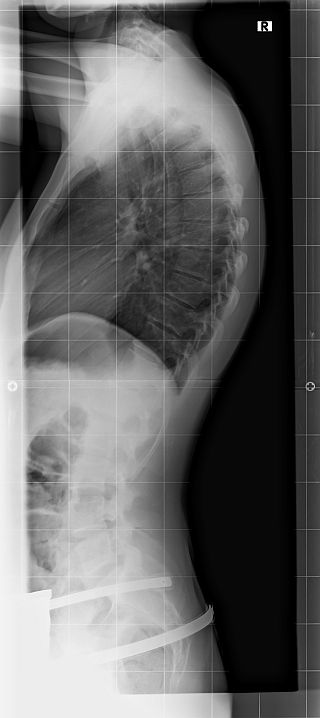

Rahmouni Korsett bei 75° Kyphose

Am Dienstag war ich zum Kontrollröntgen und möchte euch die Ergebnisse nicht vorenthalten, da sie mir wirklich mut machen.

- ohneklein.jpg (24.86 KiB) 6723 mal betrachtet

- mitklein.jpg (27.21 KiB) 6723 mal betrachtet

Das sieht wirklich gut aus, sowohl was die Hyperlordose angeht, als auch was die Hyperkyphose betrifft.

im Korsett beträgt der Kyphosewinkel 34°, was mir natürlich sehr motiviert die Tragezeiten zu steigern und auch wieder aktiv zu schrothen.